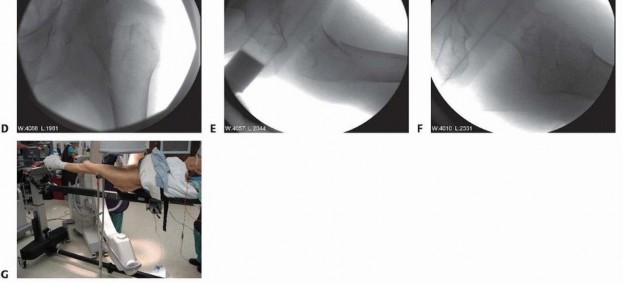

** Fracture Reduction With the patient conscientiously positioned on the fracture table, the fracture is initially reduced in the coronal plane with axial traction to reestablish fracture length and partially correct the varus malalignment ( TECH FIG 1). Abduction of the leg usually corrects varus malalignment and establishes the normal neck-shaft angle. Internal rotation of the distal extremity usually corrects the external rotation at the fracture. Internal rotation also serves to align the femoral neck parallel to the floor and assist in eventual guide pin insertion. In some instances, external rotation of the proximal fragment is necessary to achieve reduction of the rotational deformity.

### TECH FIG 1 • Fracture reduction. A. Preoperative peritrochanteric fracture. B. Position of the fracture after longitudinal traction. C. Position of the fracture after longitudinal traction and abduction applied. D. Position of the fracture after longitudinal traction, abduction, and internal rotation applied. E. Posterior fracture sag. F. Position of the fracture after longitudinal traction, abduction, internal rotation, and flexion force applied with a crutch under the leg. G. Intraoperative picture of crutch placed under distal fragment. Fracture reduction is next checked in the lateral plane. The distal femur tends to sag posteriorly while the proximal fragment is flexed by the iliopsoas. This can be corrected by placing a crutch under the femoral shaft for support. Alternatively, some fracture tables have padded attachments to support the thigh. Fracture reduction is reassessed in both the AP and lateral planes and checked for neck-shaft angle, neck anteversion, rotation, and femoral shaft sag, with a goal of obtaining a near-anatomic reduction. Acceptable parameters include normal or slight valgus reduction, less than 20 degrees of angulation on the lateral radiograph, and less than 4 mm of fracture translation. 1 If a near-anatomic closed reduction cannot be obtained, percutaneous techniques can include use of Schanz pins, a bone hook, or an elevator used to manipulate fracture fragments. In the event that reduction is still inadequate, open reduction is necessary. 407 1. ## Side Plate and Sliding Hip Screw ### Approach Because of the muscular forces exerted on the fracture fragments associated with peritrochanteric hip fractures, anatomic reduction of the fracture is close to impossible with indirect methods, especially in the coronal plane, which is often the most difficult plane to control.** Studies have shown that absolute anatomic reduction of all fragments of these fractures is not necessary for a satisfactory functional outcome. 14 The primary goal of reduction of peritrochanteric hip fractures is to reestablish a normal anatomic alignment between the proximal head and neck fragment and the distal femoral shaft in the coronal, sagittal, and axial planes. A lateral approach to the proximal femur is the preferred approach for open reduction and internal fixation of peritrochanteric femur fractures. This approach may be used whether the selected implant is a side plate, a blade plate, or a proximal femoral locking plate. The incision is centered over the lateral aspect of the femur. Its proximal extent is the palpable vastus ridge for sliding hip screw devices and just proximal to the tip of the greater trochanter for fixed-angle plates. The distal extent of the incision is made long enough to allow application of the plate.